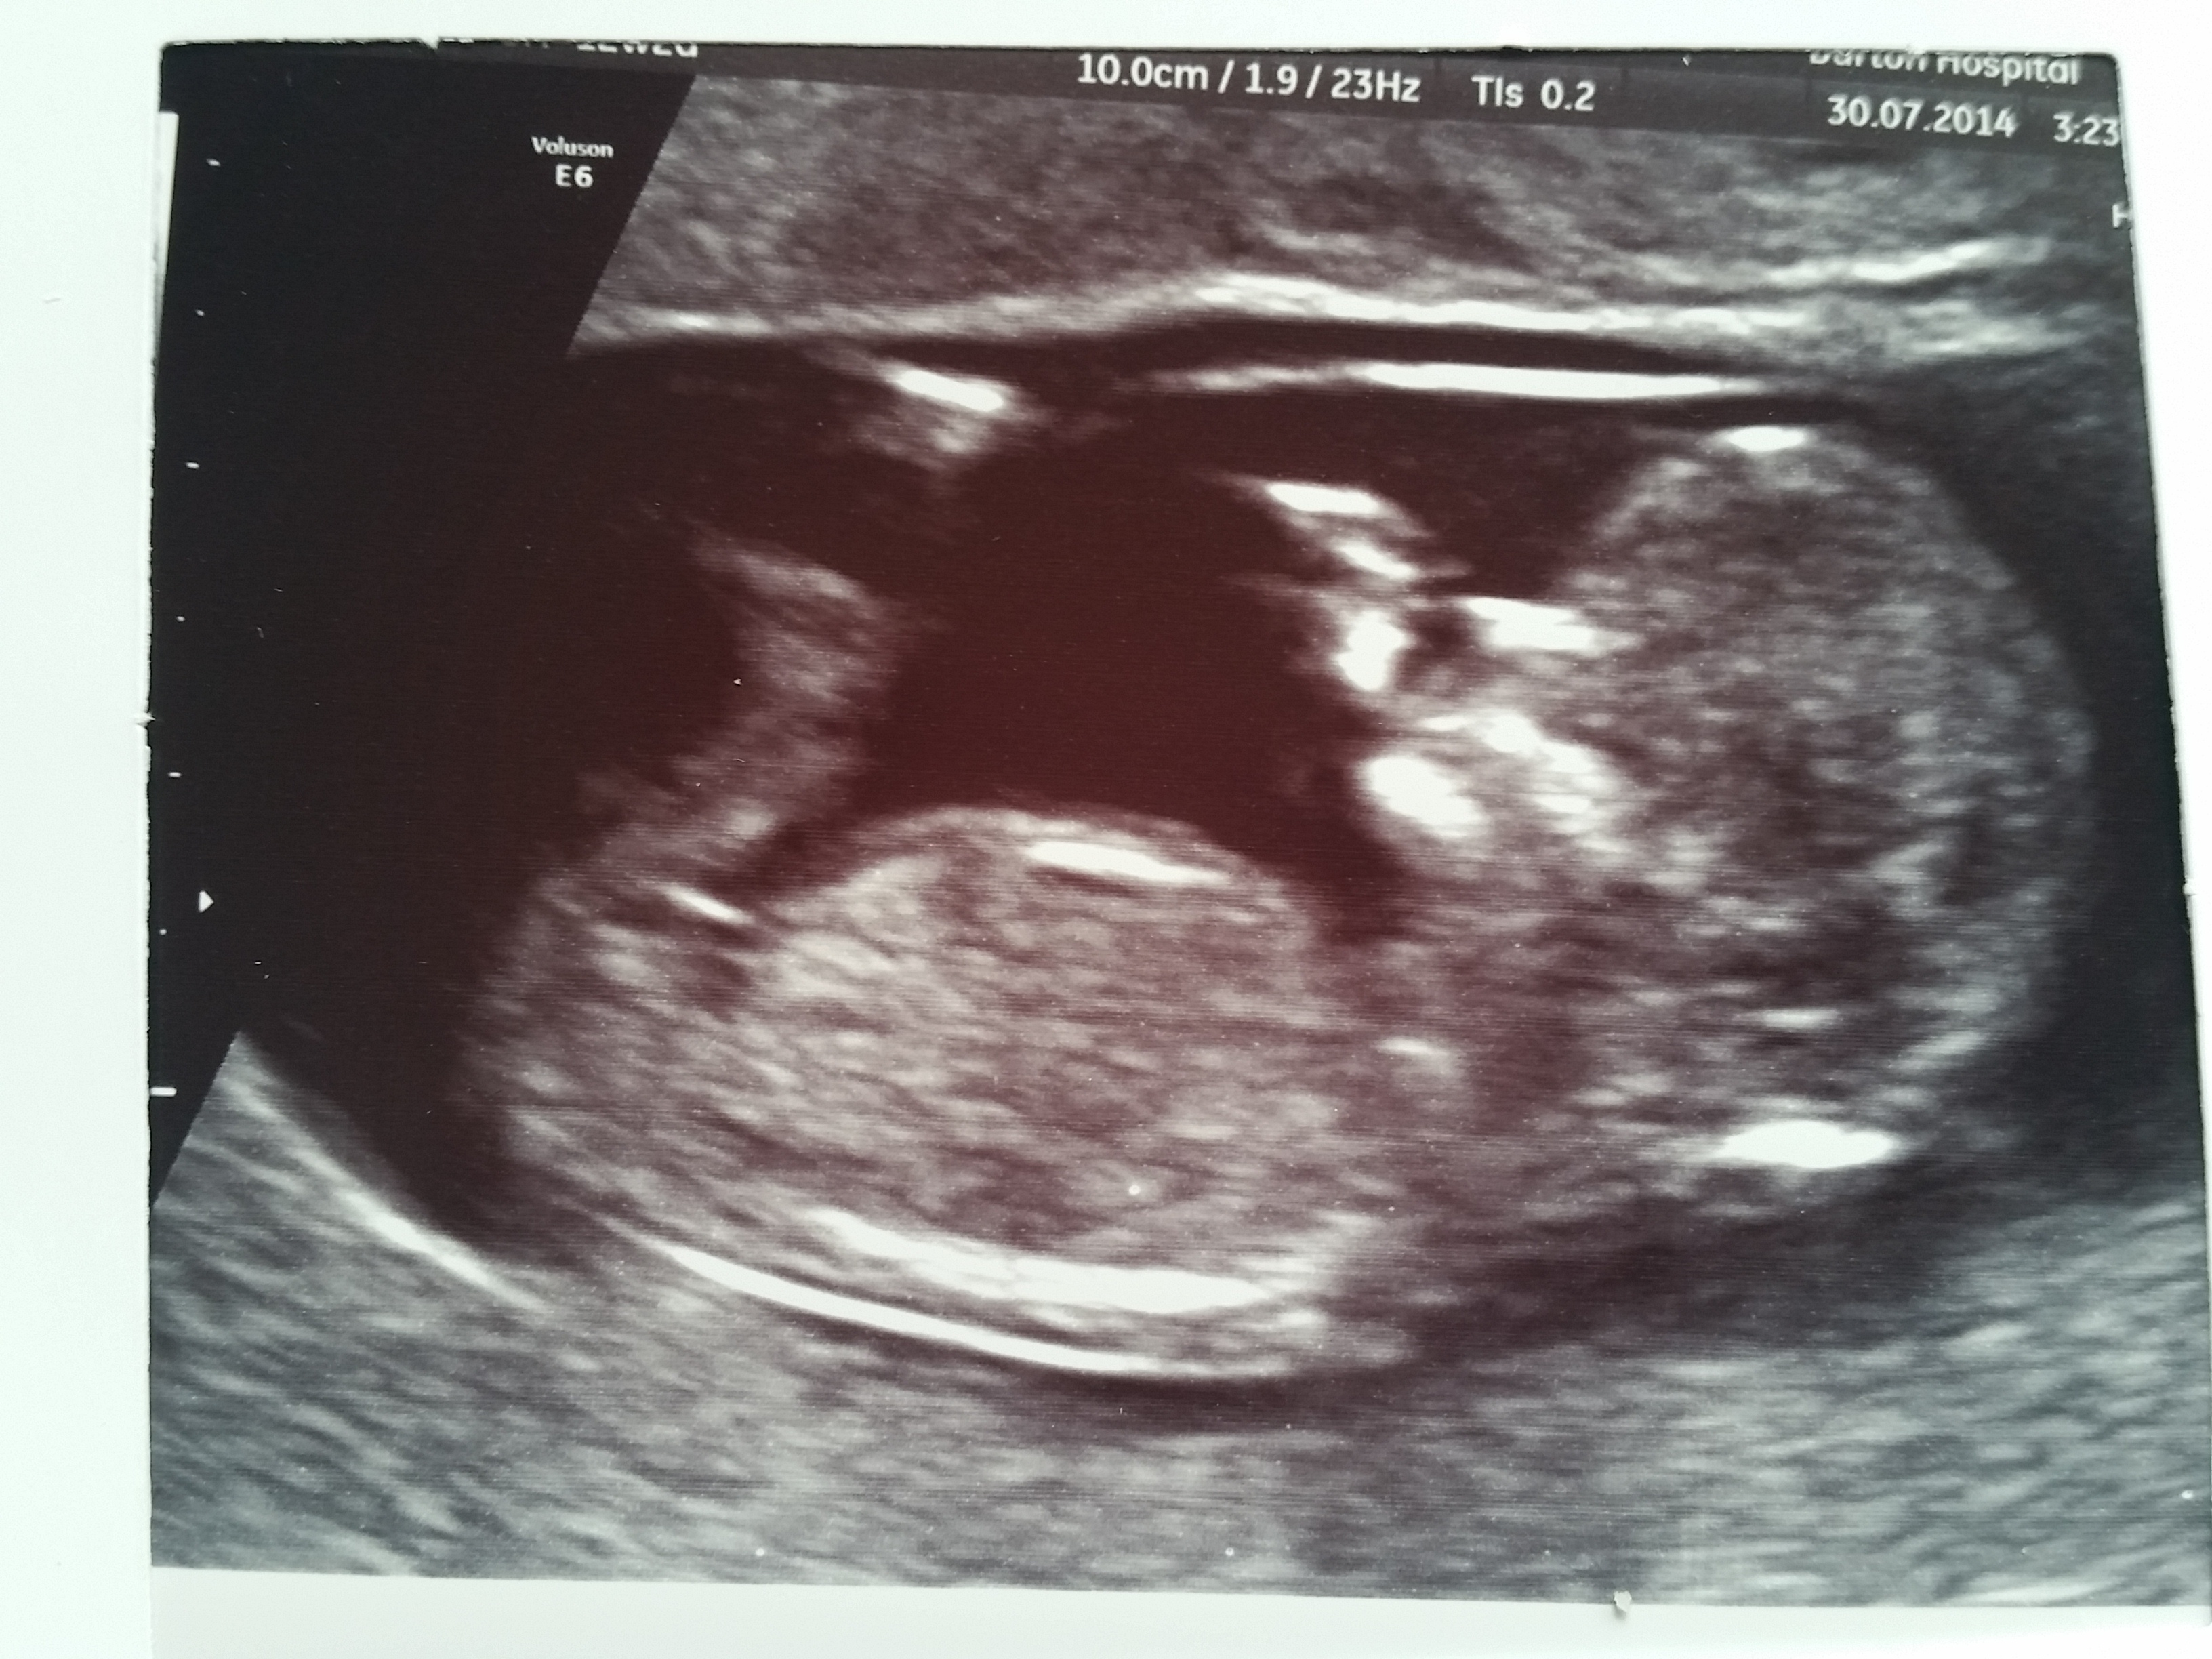

Scan was at 12+1

Very tentative girl lean based off first pic. Can't tell if the nub could be on the rise.

Any guesses based on the skull theory?

Skull theory?

Nub theory?